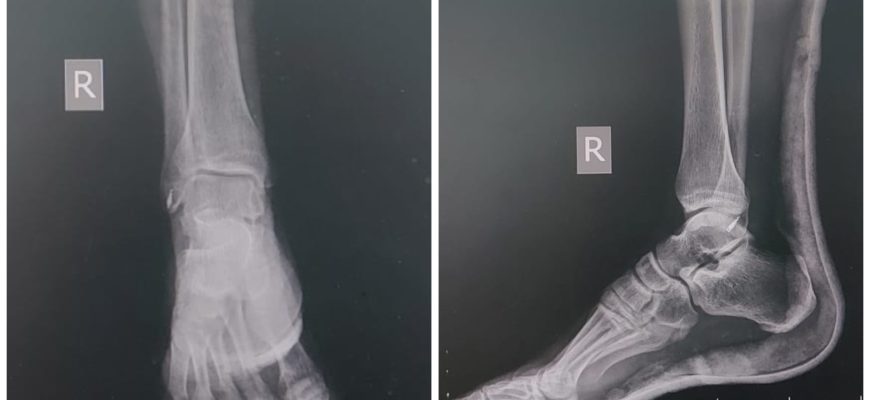

Анатомия малоберцово-большеберцового сустава: всё, что нужно знать Что такое малоберцово-большеберцовый сустав и почему его важно понимать?